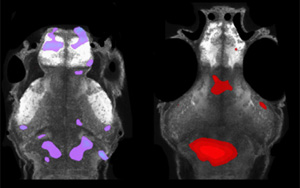

Science | 重要發(fā)現(xiàn)!斯坦福大學(xué)巧妙改造皮膚細(xì)菌,激活免疫助力抗癌

2023年4月13日,斯坦福大學(xué)Michael A. Fischbach團(tuán)隊(duì)在Science在線(xiàn)發(fā)表了題為“Engineered skin bacteria induce antitumor T cell responses against melanoma”的研究論文,該研究通過(guò)表達(dá)固定在分泌蛋白或細(xì)菌表面蛋白上的腫瘤抗原改造皮膚細(xì)菌表皮葡萄球菌來(lái),測(cè)試其驅(qū)動(dòng)抗腫瘤免疫反應(yīng)的能力。在定植后,工程化表皮葡萄球菌能誘導(dǎo)產(chǎn)生腫瘤特異性T細(xì)胞,該T細(xì)胞成熟后能在血液中循環(huán),并進(jìn)而浸潤(rùn)局部和轉(zhuǎn)移性腫瘤病變處,發(fā)揮